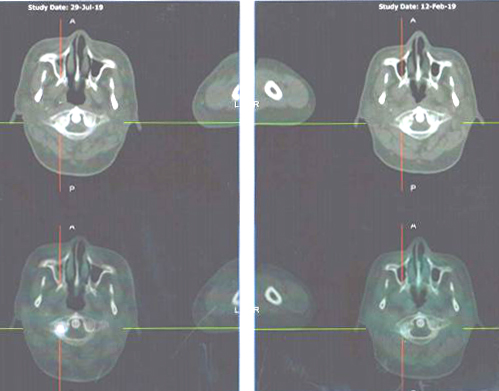

Mari kita lihat hasil pemindaian PET-nya.

Perbandingan hasil pemindaian: 29 Juli 2019 (baris atas) vs 12 Februari 2019 (baris bawah)

Perbandingan hasil pemindaian: 29 Juli 2019 (baris kiri) vs 12 Februari 2019 (baris kanan)

Ada yang salah dengan tulangnya? Pemindaian pada 29 Juli 2019 (kolom kiri) tampaknya lebih serius daripada pemindaian yang dilakukan pada 12 Februari 2019 (kanan).

Hasil PET scan pada 29 Juli 2019